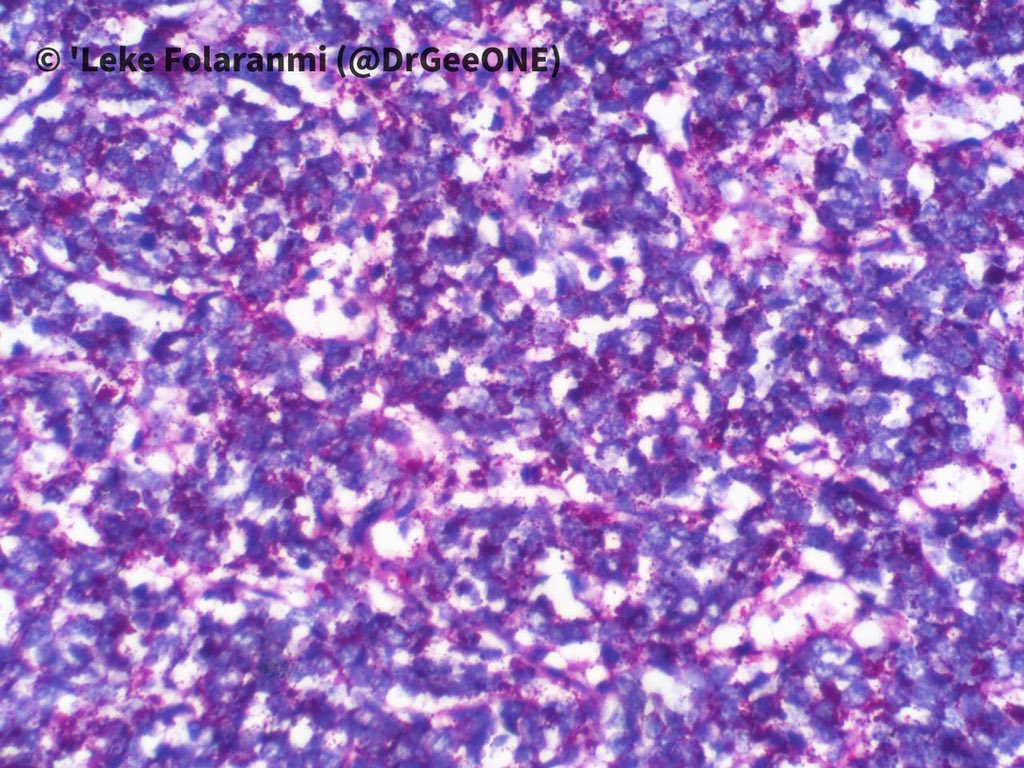

A male in his 20s with huge intrathoracic mass.

Duration: 2 years

❗️No IHC done

High power pictures of H/E and PAS sections